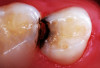

(6.) After exposure of disto-occlusal caries, SDF is applied, followed by a coating of fluoride varnish.

Figure 6

(7.) After exposure of disto-occlusal caries, SDF is applied, followed by a coating of fluoride varnish.

Figure 7

(8.) After exposure of disto-occlusal caries, SDF is applied, followed by a coating of fluoride varnish.

Figure 8

(9.) After exposure of disto-occlusal caries, SDF is applied, followed by a coating of fluoride varnish.

Figure 9